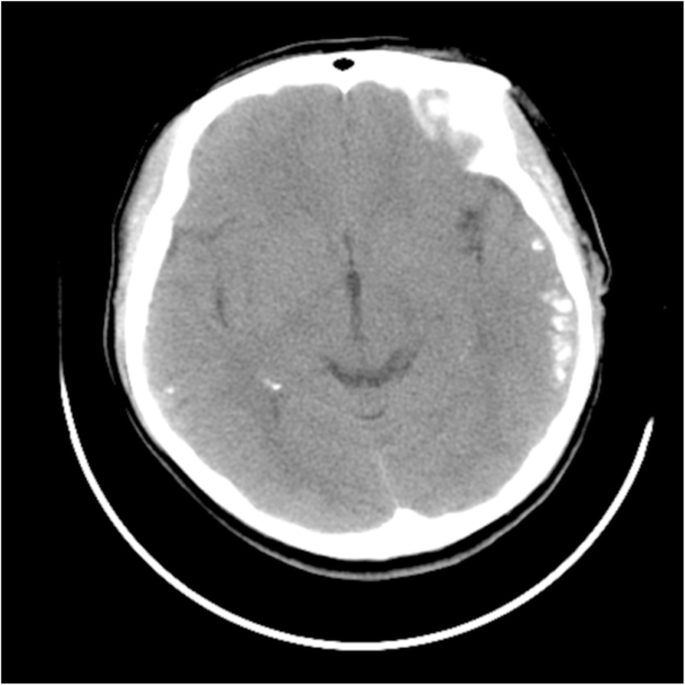

A 25-year-old female nurse that worked in our department was admitted to hospital for a seizure. A CT scan of her brain showed bilateral temporal calcifications (Fig. 1). The patient had no prodromal features (history of infection or previous flu-like symptoms) and denied drug or alcohol ingestion. In our preceding daily work contacts, we had observed her strange personality and behavior. On general examination, we found no nevus flammeus on her face and supposed she had an atypical Sturge-Weber syndrome (SWS). Laboratory investigations showed that her complete blood count, renal and liver function, blood glucose, serum calcium, serum phosphorus, and parathyroid hormone were within the reference ranges. The screening tests for Hepatitis B, Hepatitis C, human immunodeficiency virus, and syphilis were negative. Her thyroid function test showed increases of anti-thyroid peroxidase antibodies (TPO-Ab) (> 1300 U/mL) and anti-thyroglobulin (209.60 U/mL), while fT3, fT4 and TSH were in normal rang. Ultrasound investigation revealed a swollen thyroid. The findings of the brain magnetic resonance imaging (MRI) findings were consistent with those of the head CT. 12-h video electroencephalogram revealed spikes and spike-slow waves discharged from left temporal electrodes with spread to the contralateral hemisphere during the sleep stage. She was administered antiepileptic medication (levetiracetam) which terminated her seizures, and she returned to work.